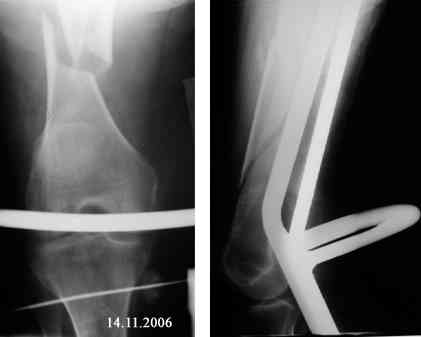

Re: Оскольчатый перелом бедра. Помогите определиться с дальнейшей тактикой

Представляю вашему вниманию снимки в динамике